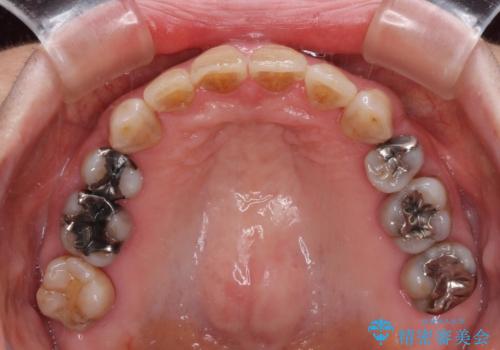

長年気にされていた口元の突出感が改善されたため、もっと若い時分に矯正をすればよかったと思われていました。

- 突出した口元を引っ込めることを希望して来院された患者様です。

上下左右第一小臼歯4本を抜歯して、口元を改善するワイヤー矯正を行うこととしました。